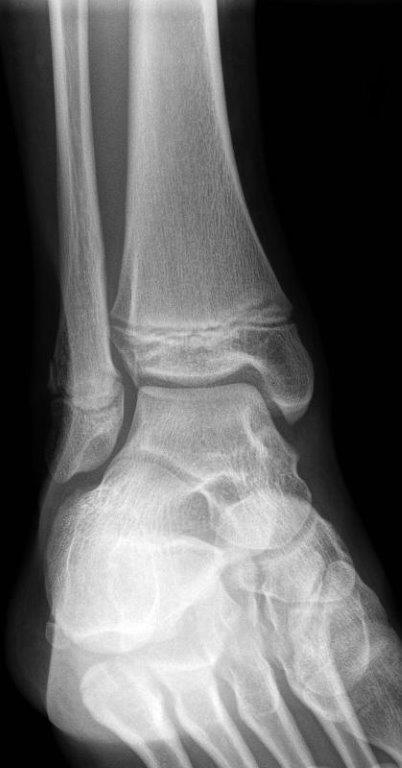

Salter Harris I fracture of fibula

Salter Harris 1 fracture of fibia

• No formal follow up required.